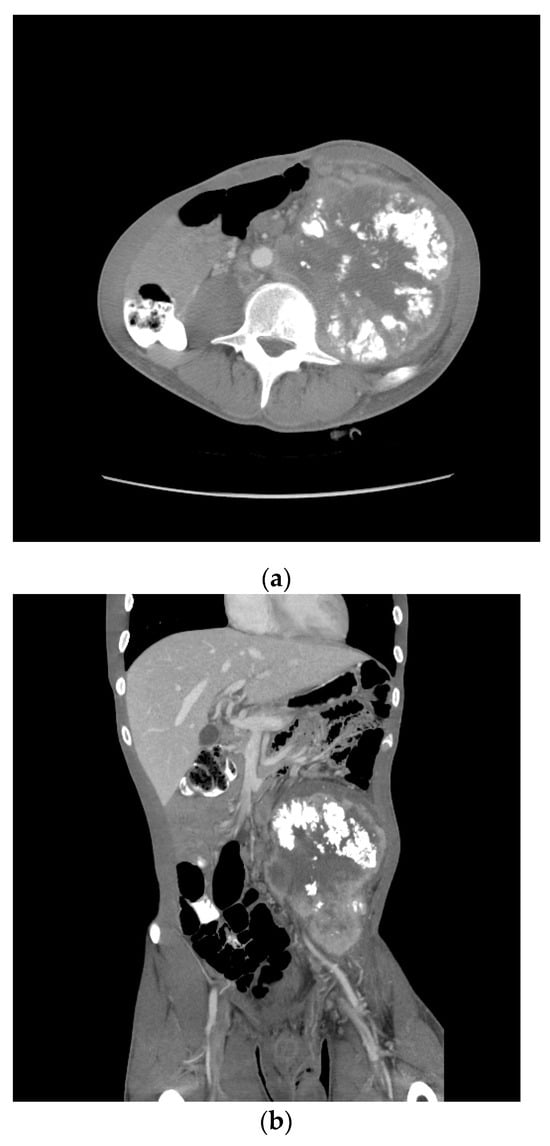

| Patient NSGCT Type | Status | Pathology of Primary | Stage at Time of Diagnosis | S-YSTemic Chemo | Date: Pathology after Chemo |

|---|---|---|---|---|---|

| 1 ETT | Cured | 100% S (elevated AFP) | IIX | BEP x1, VIP x3, paclitaxel (docetaxel), doxorubicin, gemcitabine, | 6/2012: 90% T, 10% ETT + adenocarcinoma |

| 2 S-YST | Cured | 5% E, 90% S, 5% Y | IIIC | BEP x4 | 5/2018, 4/2019, 4/2020: 99% S-YST + 1% T |

| 3 ETT | Cured | 80% ETT, 20% T | IIC | BEP x3 | 1/2018: T w/minute ETT |

| 4 S-YST | Died | NA Y in met | IIIC | BEP x4 | 9/2016: T 1/2021: S-YST |

| 5 ETT | Died | 100% E | IIIA | BEP x1, EP x3, TIP x4, POMB x2, ATP x4, TIP x1/HDC + SCT | 7/2019: Embryonal 11/2019: ETT 1/2020: Choriocarcinoma |

| 6. ETT | Died | 99% E, 1% T | IIIA | BEP x3, TIP x3, ATP | 9/2018: E, C 7/2019, 8/2019: 60% ETT + squamous cell carcinoma |

| 7 S-YST | Died | NA i(12p)+ in met | IIC | BEP x2, XELOX, ATP x2 | 8/2019: S-YST (Unresectable) |